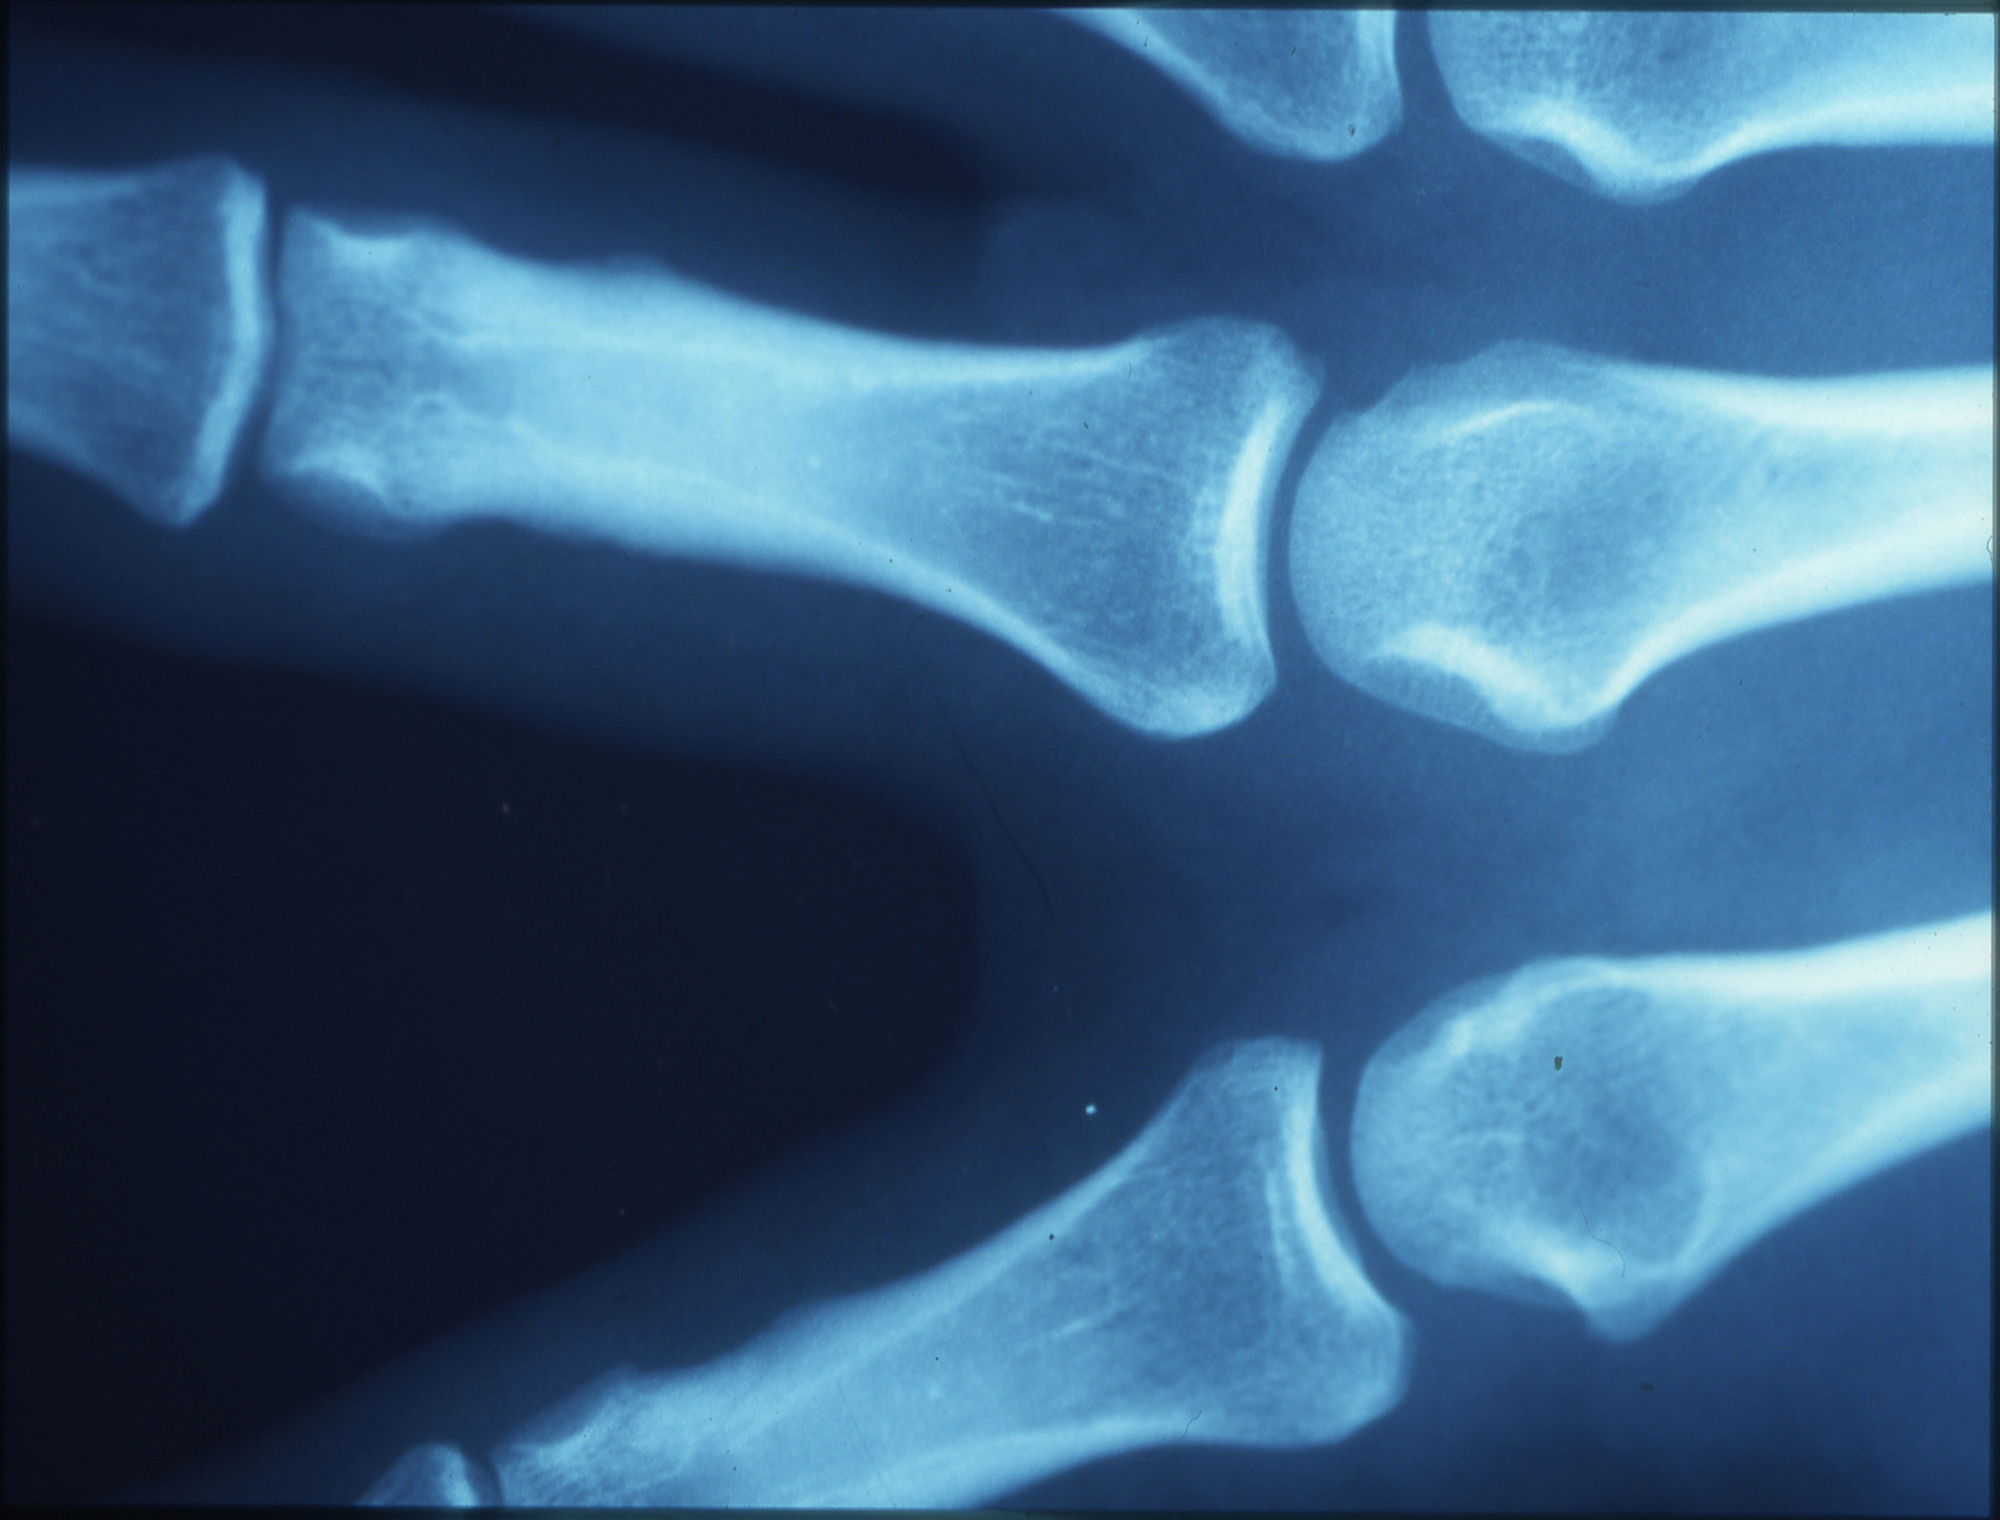

Cartilage naturally becomes thinner and less flexible with age. In younger athletes, cartilage has more water content and a stronger structure, which helps absorb impact during movement. Over time, this structure weakens.

As cartilage loses its smooth surface, friction within the joint increases. This can lead to discomfort during movement and may affect performance over time. The joint may also become less stable, making it harder to maintain the same level of activity.